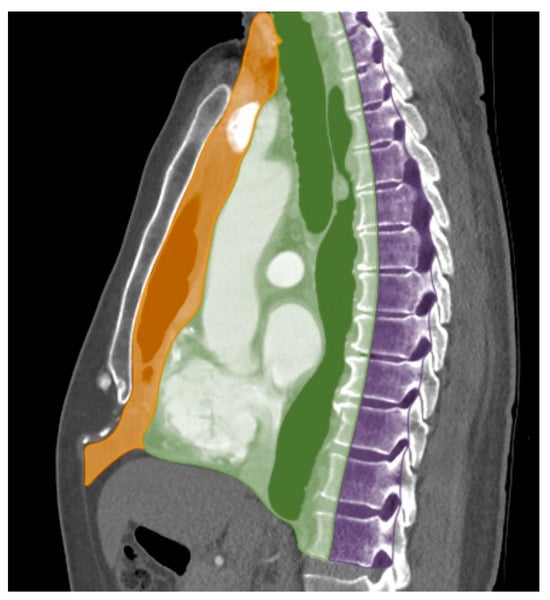

| Compartment | Boundaries |

|---|---|

| Prevascular | Anterior: sternum |

| Posterior: anterior surface of pericardium as it wraps around the heart | |

| Superior: thoracic inlet | |

| Inferior: diaphragm | |

| Lateral: mediastinal pleura | |

| Visceral | Anterior: posterior boundaries of prevascular compartment |

| Posterior: vertical line connecting a point on each thoracic vertebral body 1 cm posterior to its anterior margin | |

| Paravertebral | Anterior: posterior boundaries of the visceral compartment |

| Posterolateral: vertical line against the posterior margin of the chest wall at the lateral margin of the transverse process of the thoracic spine | |

| Inferior: diaphragm |